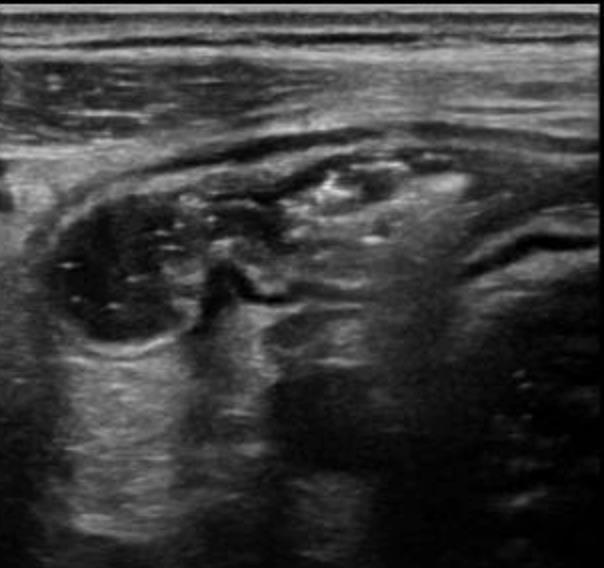

• Gastrointestinal (GI) symptoms (abdominal pain, diarrhoea and vomiting) are prevalent in MIS-C

• Abdominal pain in 62%

• Up to 90% any GI symptom

• Anumber of studies have described abdominal imaging findings including ascites, bowel wall thickening and mesenteric lymphadenopathy

MIS-C